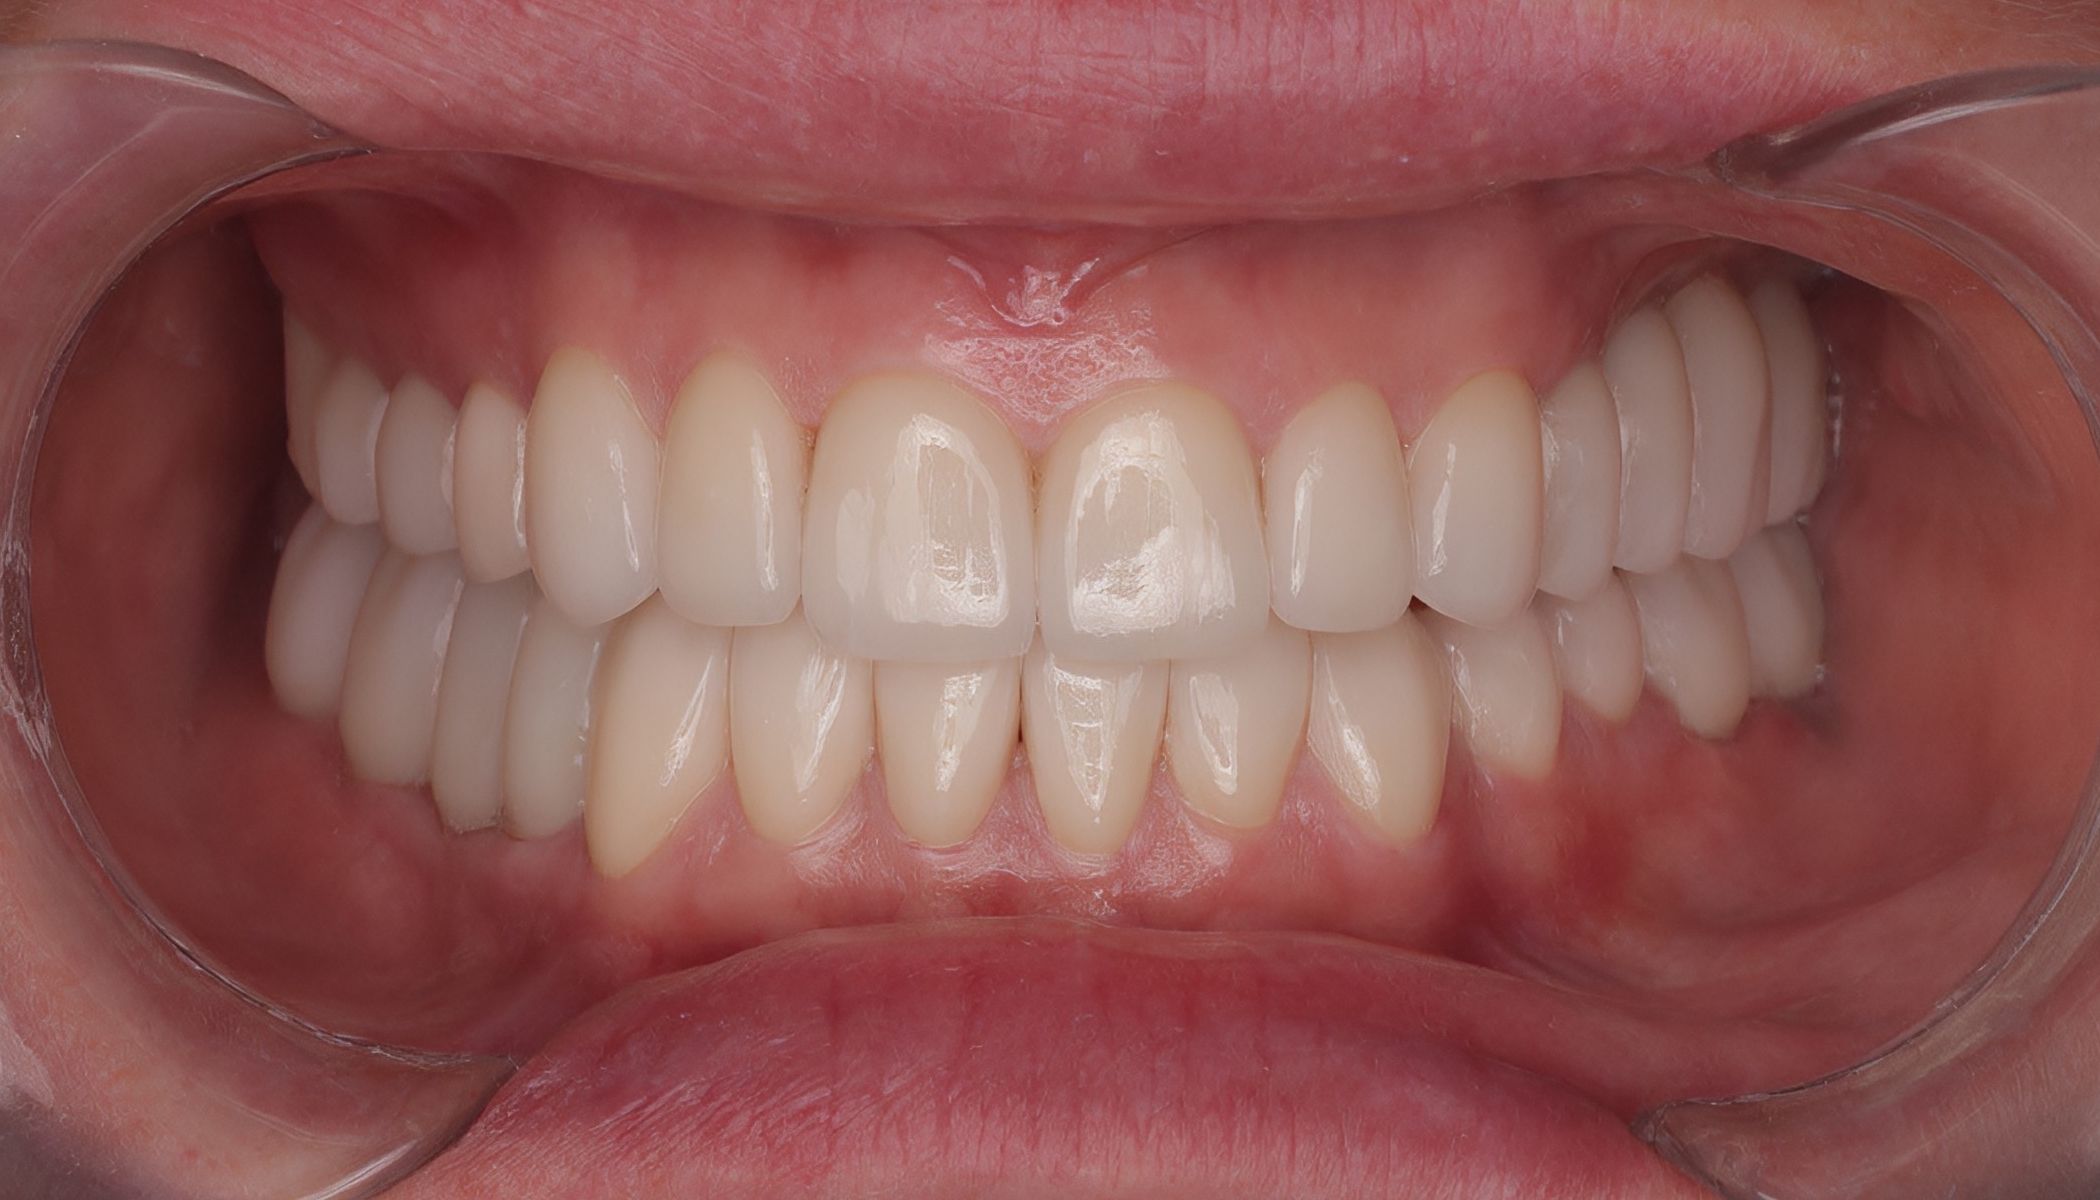

На третьем этапе, после двухмесячного периода адаптации, временные реставрации были заменены на постоянные безметалловые конструкции. В результате комплексного подхода удалось полностью восстановить эстетику и функциональность зубочелюстной системы. Пациентка вновь обрела полноценную улыбку и улучшенную способность пережёвывания пищи. Это положительно сказалось на качестве её жизни. Таким образом, проведённое лечение эффективно решило проблему отсутствия жевательных зубов и изменения формы остальных, улучшив как внешний вид, так и функциональные параметры ротовой полости.